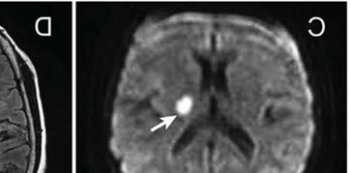

多發(fā)腦梗死是非常嚴重的疾病,一旦發(fā)病之后患者會出現(xiàn)半身不遂,語言不利,肢體麻木,頭痛等癥狀,還有的患者甚至還會出現(xiàn)昏厥等癥狀,所以一定要盡早到醫(yī)院去接受治療。

如果是輕微的多發(fā)性腦梗死的患者在住院之后醫(yī)生會立馬用肝素法華林等藥物能夠有效的減輕病癥,除此之外還需要考慮患者是否有高血壓,高血糖,高血脂等疾病,然后及時的用降壓降糖的藥物調(diào)節(jié)身體的各項指標(biāo),患者在整個治療階段是需要及時的將血管疏通的,否則人體的大腦功能會受到非常嚴重的影響,如果患者出現(xiàn)呼吸衰竭的現(xiàn)象,醫(yī)生會馬上吸氧,在患者出院之后仍然是需要繼續(xù)做康復(fù)性的訓(xùn)練的,多運動也是可以讓患者逐漸的恢復(fù)正常的生活自理能力。